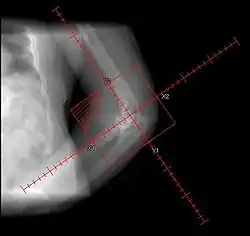

Brooker Classification: (radiographic)

• I - islands of bone within the soft tissue (clinically silent)

• II - bone spurs from the pelvis or proximal femur; >= 1 cm gap between opposing surfaces (clinically insignificant)

• III - bone spurs from the pelvis or proximal femur; < 1 cm gap between opposing surfaces (clinically significant)

• IV - ankylosis (clinically significant)